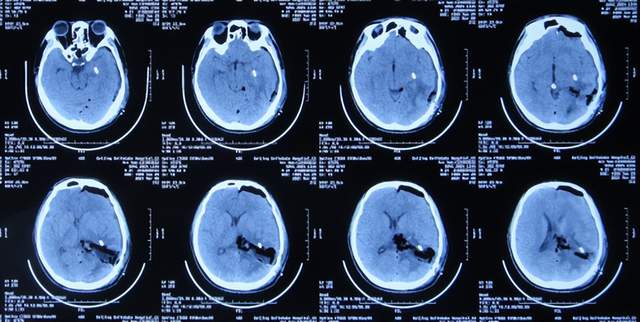

入院后7天即2021年1月20日,进行了颅内占位切除术,留置引流管(图-5)。

图-5:2021年1月20日头颅CT

颅内占位切除术后次日即2021年1月21日,查头颅CT示脑瘤术后改变(图-6)。

图-6:2021年1月21日头颅CT

颅内占位切除术后第2天即2021年1月22日,头痛基本消失,脑瘤病理回报脑膜瘤;查头颅CT示脑室周水肿(图-7)。

图-7:2021年1月22日头颅CT

但术后第4天,出现发热,体温约在38度以上,最高39度,给予对症治疗。

脑膜瘤术后第5天即2021年1月25日,查头颅是示水肿减轻(图-8)。

图-8:2021年1月25日头颅CT

术后第7天即2021年1月27日,拔除脑室外引流管(图-9),改行腰大池引流并给予抗感染治疗。

图-9:2021年1月27日头颅CT

继续抗感染治疗1周的时间,仍精神差,食欲差,间断发热,期间3次查头颅影像(2021年1月29日头颅核磁增强(图-10)、2021年1月31日头颅CT(图-11)、2021年2月3日头颅核磁增强(图-12)均示颞角逐渐有扩张,有感染。

图-10:2021年1月29日头颅核磁增强

图-11:2021年1月31日头颅CT

图-12:2021年2月3日头颅核磁增强